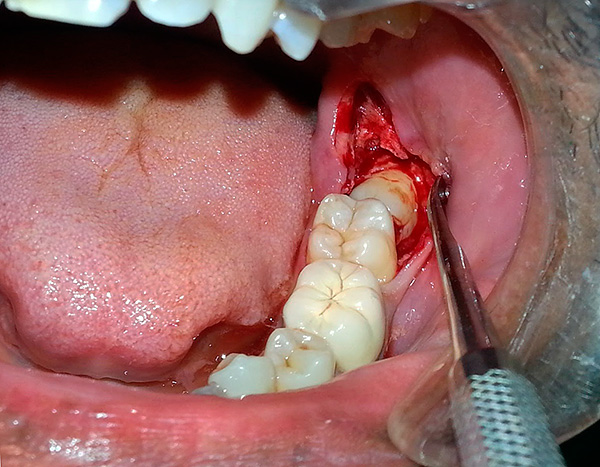

- Creazione dell'accesso al dente retinato (incisione della gomma con un bisturi, rimozione del tessuto osseo con taglierine con raffreddamento. In alcune cliniche possono utilizzare un bisturi laser);

- Estrazione di un dente del giudizio da parte degli elevatori o segatura con frese in parti e eliminazione graduale di ogni pezzo. Non aver paura di tagliare un dente dalla mascella, poiché accelera quasi sempre il lavoro 2-3 volte e ti consente di ottenere un risultato positivo in meno tempo. Rispetto alla segatura, è molto più spiacevole scavare un dente retinato con uno scalpello;